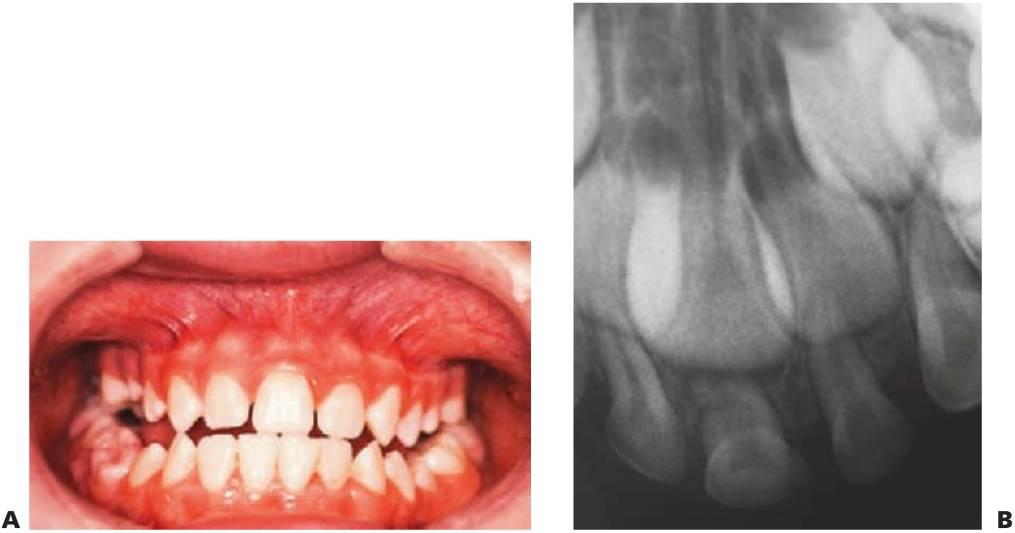

Los dientes supernumerarios surgen como resultado de una geminación de la lámina dental que se produce de forma esporádica o se heredan, como sucede con la displasia cleidocraneal (fig. 9.8).

La forma de los dientes puede recordar a la forma de las piezas normales (diente suplementario), es decir, incisiforme, caniniforme o molariforme; de no ser así, sería cónico o tuberculado.

Habitualmente se presenta como consecuencia del fallo en la erupción de uno o más dientes permanentes y en general presenta formas cónicas o tuberculadas.

- Erupción fallida o ectópica de un diente permanente (fig. 9.8B).

- A menudo erupcionan dientes cónicos que se pueden extraer con mucha facilidad (fig. 9.8A).

- Los dientes tuberculados o cónicos invertidos requieren extracción quirúrgica (fig. 9.8D) tan pronto como sea posible para permitir la erupción sin obstáculos del diente permanente.

- Resulta esencial localizar la posición del diente que debe extraerse antes de la cirugía. Pueden realizarse radiografías periapicales que emplean la técnica del desplazamiento del tubo (tube-shift) para localizar el diente, pero siempre entrañan la posibilidad de errores e interpretaciones erróneas. De la misma manera, pueden utilizarse radiografías panorámicas y oclusales maxilares estándar. La proyección oclusal de vértice permite obtener una muestra más precisa de la localización horizontal y anteroposterior, por lo que es la preferida (fig. 9.8C) para ayudar a determinar el procedimiento quirúrgico óptimo. Algunos centros prefieren no utilizar esta vía debido a una excesiva radiación en el cráneo.